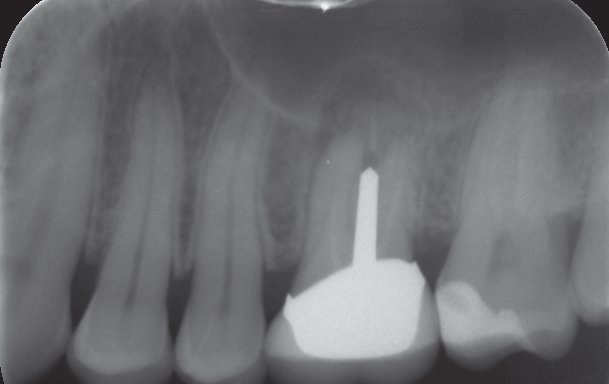

02/10 - X-ray control before implantation with partially regenerated extraction socketInternal sinus lift with maxresorb® inject - case Dr. Frank Kistler

-